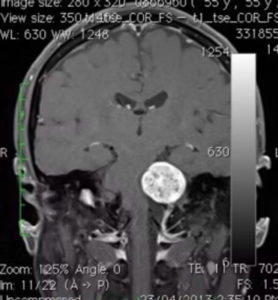

磁力共振影像診斷

磁力共振醫學影像檢查,有助於明確診斷及鑑別小腦腦橋角區域的腫瘤,例如腦膜瘤、表皮樣囊腫、三叉神經鞘瘤等的鑑別。

聽覺神經瘤的磁力共振影像特點:

腫瘤對小腦、腦幹的壓力。

可見聽覺神經瘤由內聽道向內側長出來,像蝌蚪的尾巴一樣。